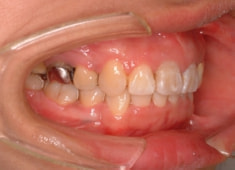

治療開始から1年8ヶ月後